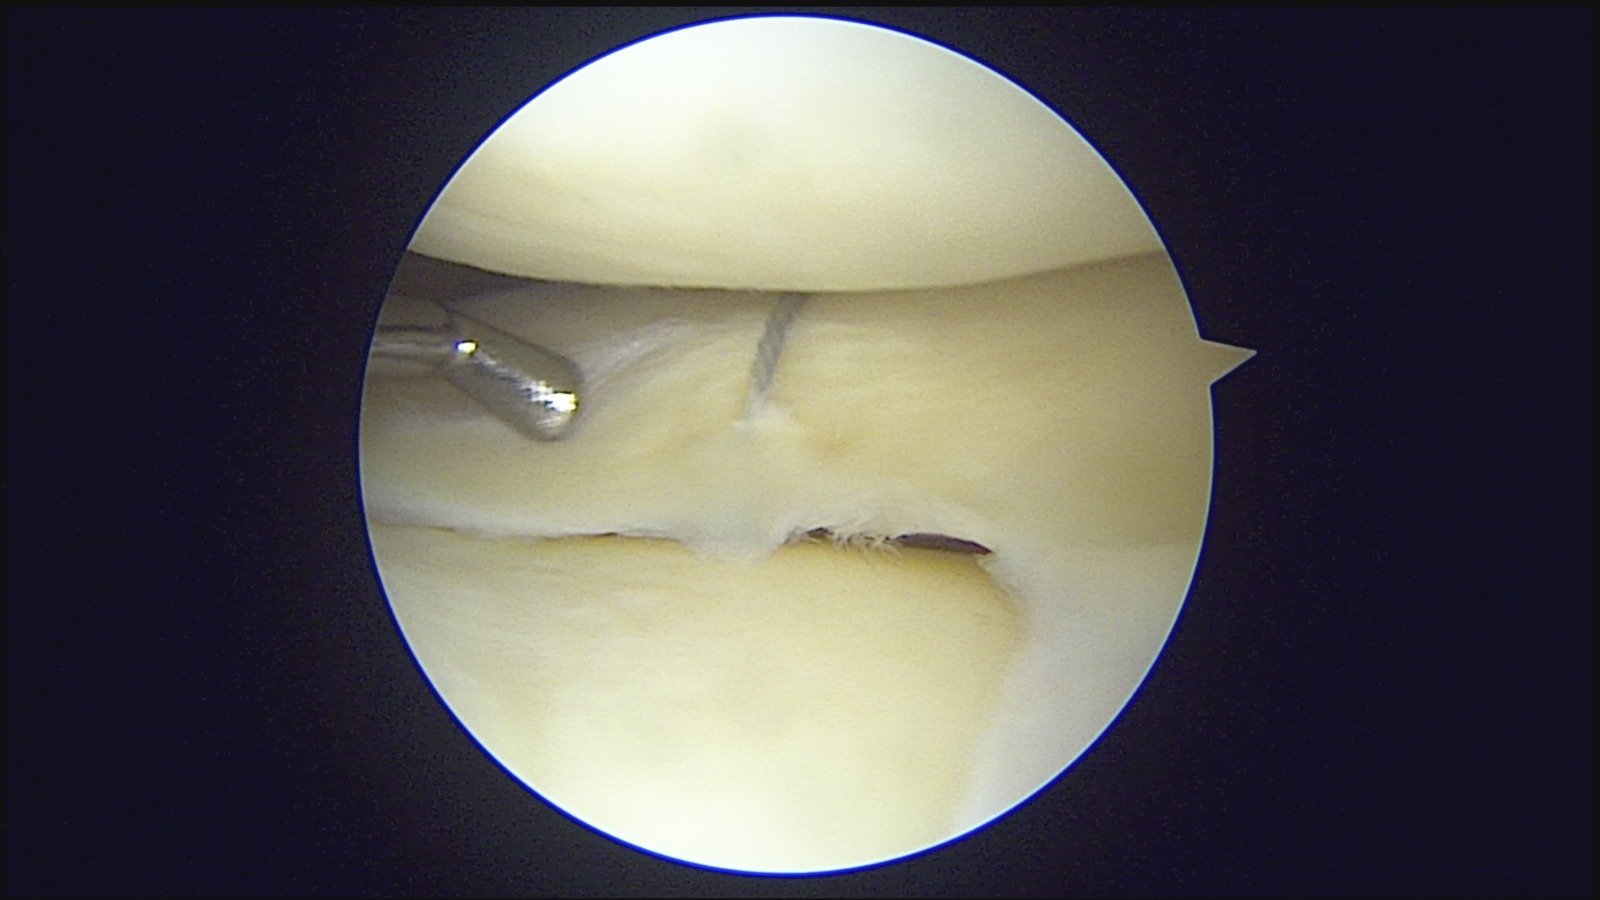

GalleryShoulder rotator cuff repair Meniscus root repair Meniscus repair Bankart repair for recurrent shoulder dislocation ACL reconstruction Machines Instruments